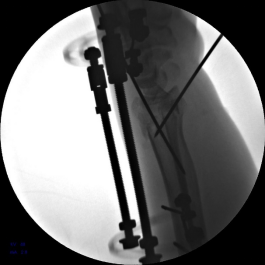

2.安装外固定架,调节螺母纵向牵拉,初步恢复桡骨高度

3.背侧穿针撬拨,继续恢复桡骨高度